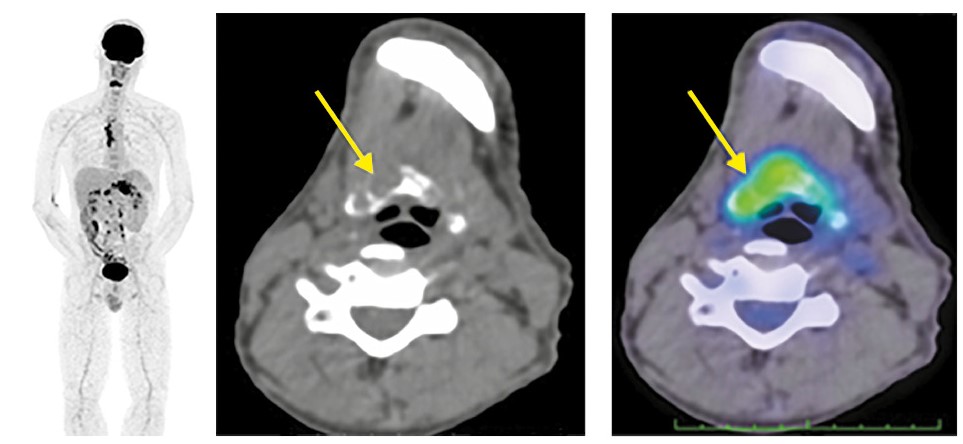

По результатам ПЭТ/КТ выявлена положительная динамика в виде склеротического уплотнения кортикального слоя подъязычной кости на всем протяжении с отсутствием гиперфиксации РФП (рис. 4).

Рис. 4. Пациент Т., 54 года. На аксиальных и сагиттальных КТ- и ПЭТ/КТ-проекциях отмечается склеротическое уплотнение кортикального слоя подъязычной кости с полным регрессом фиксации РФП (стрелки).

Констатирована прогрессия опухолевого процесса. Назначена ПХТ 2-й линии по схеме DCF. Общая продолжительность жизни с момента начала лечения составила 13 мес. Следует отметить положительный эффект в виде частичной регрессии при вторичном поражении подъязычной кости благодаря ПХТ.